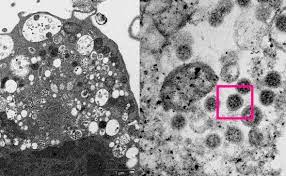

"Государственный научный центр вирусологии и биотехнологии "Вектор" в лабораторных условиях заразил культуру клеток Vero E6 штаммом "омикрон" коронавируса для исследования его морфологических характеристик, т.е. формы, размера, наличия структур находящихся на поверхности и так далее", - говорится в сообщении.

Отмечается, что клетки были отделены от поверхности специальных флаконов, в которых они выращивались, на шестые сутки после заражения вирусом.

"После подготовки пробы клетки были залиты в смесь эпоксидных смол. С этих блоков сделаны очень тонкие срезы, чтобы полученные образцы были прозрачны для электронного пучка и их можно было рассматривать в электронном микроскопе. На снимках – везикулярные структуры (пузырьки), которые в большинстве случаев представляют собой расширенные канальцы внутриклеточной сети, при участии которой происходит синтез и транспорт белков, липидов и других веществ, необходимых для жизни клетки", - сообщает Роспотребнадзор.

Добавляется, что белки, из которых состоит вирус, синтезируются в цитоплазме, а впоследствии скапливаются у поверхности этих пузырьков и при соблюдении определенных физических и химических условий проникают внутрь, приобретая при этом дополнительную оболочку.

"Мембрана пузырьков в том месте, где формируется вирусная частица, претерпевает изменения. В нее встраиваются структурные белки вируса, которые впоследствии будут представлены на его поверхности и будут определять его поведение при встрече с другой клеткой", - говорится в сообщении.

Уточняется, что в случае со штаммом "омикрон" необычно то, что вирус собирается медленно и в отличии от других штаммов не вызывает массовой гибели клеток на 6-е сутки инфекции. Состояние клеток при заражении штаммом омикрон соответствует тому, что можно увидеть на вторые-третьи сутки при заражении другими штаммами.